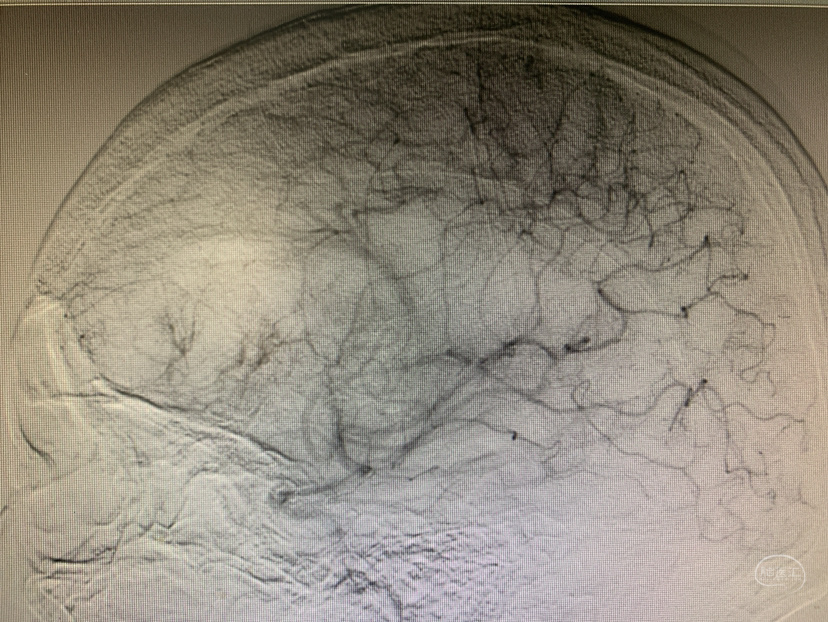

术前造影

神志昏迷双瞳散大对光反射迟钝入院,入院后甘露醇脱水加地米静滴后患者神经功能有改善,能摸索定位,瞳孔反射改善。考虑占位大直接切除可能出血多,拟术前栓塞处理,但造影发现栓塞不易风险高后放弃栓塞。